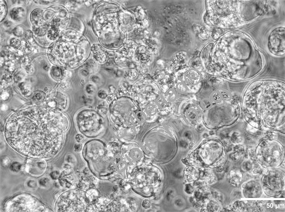

乳腺癌芯片:在脂肪细胞构建的“乳腺环境”中嵌套肿瘤球体,并模拟血管灌注抗癌药物(如阿霉素)。实验证实,药物通过血管扩散可显著缩小肿瘤体积(p ≤ 0.05),为个性化治疗提供新平台。